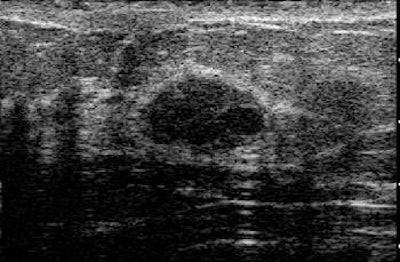

![]() |

| Fibroadenoma with elasticity score of 2 in 39-year-old woman. US images were obtained in transverse plane. Left: On conventional B-mode image, lesion was classified as BI-RADS category 3. |